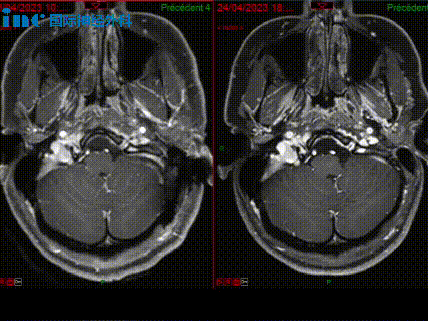

左侧为术后影像,右侧为术前影像,两者对比可清晰看到肿瘤的去除情况。